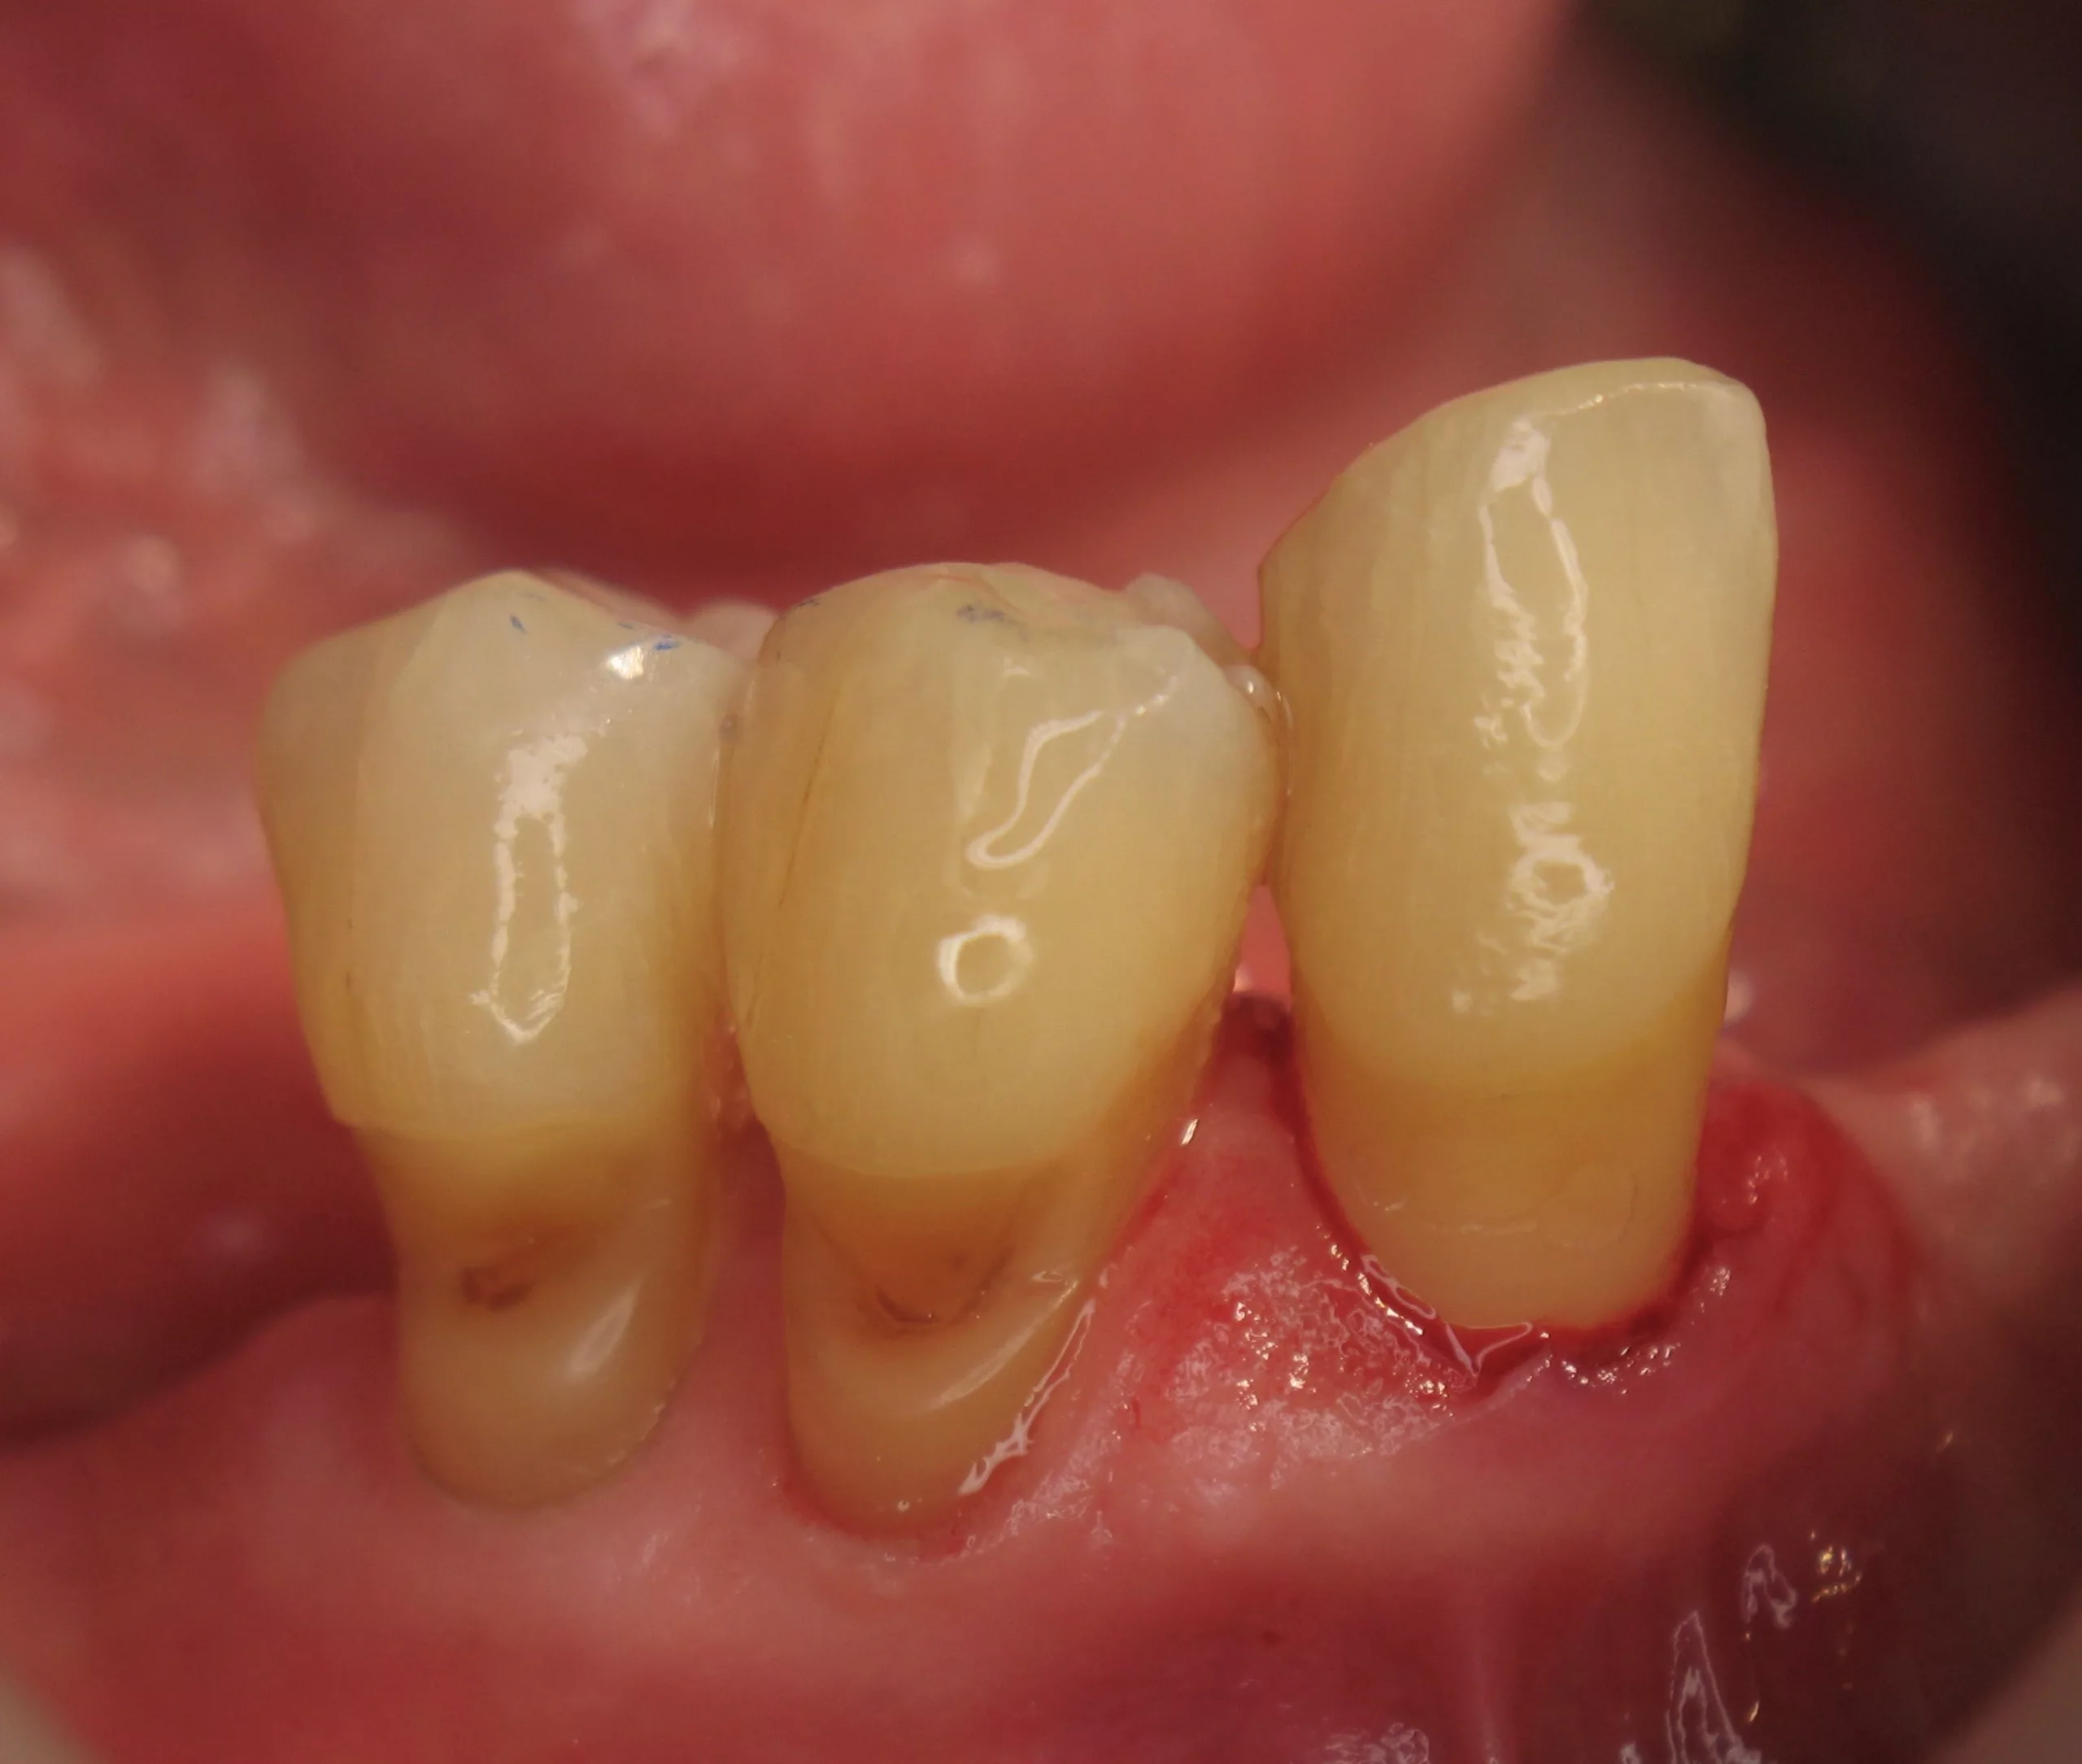

Der Patient (männlich, 72 Jahre alt) war vor der Behandlung bereits seit vielen Jahren parodontal erkrankt. Aufgrund der Einnahme verschiedener Medikamente litt er zudem unter Mundtrockenheit, so dass der Speichel seine wichtige Funktion als schützender Puffer für den Zahnschmelz nur ungenügend erfüllen konnte. Der Patient wies ausgeprägte Zahnhalsdefekte mit Rezessionen auf (Abb. 1 u. 2) und reagierte nach der Parodontalbehandlung schmerzempfindlich auf Heißes, Kaltes oder Süßes. Zudem zeigten sich mehrere kariöse Läsionen.

Klinisch war eine Stabilisierung der kariösen Läsionen sichtbar (Abb. 6). Angesichts der generell schwierigen Mundhygienesituation bei Senioren sowie ihrem höheren Risiko für freiliegende Zahnhälse und Karies, kann eine Zahnpaste mit erhöhter Fluoridkonzentration wie Duraphat® Fluorid 5mg/g als Mittel der Wahl in der Seniorenzahnmedizin gelten.